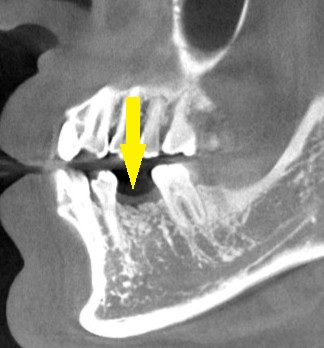

CTを撮影してみると、確かに、骨幅が狭く、十分な骨の厚みを確保してインプラントを長期に安定した状態にしたいとなると、骨を増やす手術が必要でした。

人工骨を使用しての骨造成術を併用して、インプラント埋入を行なうことで了承されましたので、本日、同手術を施行しました。

下の写真に手術前後のCTを示します。